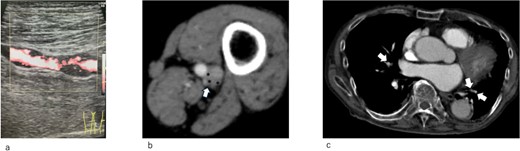

An IVCF was inserted into the inferior vena cava (IVC) using the right internal jugular venous approach. After performing IVC venography (Fig. 2a) using a driver sheath, the IVCF was attempted to deployed. However, the IVCF did not open (Fig. 2b). To retrieve the unopened filter, a plunger was pulled; however, the IVCF and plunger detached (Fig. 2c). We attempted to remove the IVCF via a right femoral venous approach using a snare. However, the snare did not pass through the IVCF because the tip of the leg was attached to the IVC wall or gonadal vein ostium. The hemodynamics of the patient worsened during the procedure. Therefore, we decided to quit additional endovascular retrieval and place a new IVCF. A new IVCF was placed to hold the unopened IVCF at the proximal (head) portion of the unopened IVCF through a right jugular approach (Fig. 2d). An unopened IVCF was placed with pulling the delivery sheath (Fig. 3).

Intraoperative radiographic fluorescence imaging. (a) Pre-deployment venogram of the inferior vena cava (IVC) demonstrating appropriate positioning of the delivery sheath within the IVC prior to inferior vena cava filter (IVCF) placement. (b) The IVCF is not open, and the legs of the IVCF are folded. The IVCF is hung on a plunger. The arrow indicates the tip of the sheath. The arrowheads indicate the folded IVCF legs. (c) The IVCF could not be retrieved because it is detached from the plunger. The arrow indicates the tip of the sheath. The arrowheads indicate the folded IVCF legs. (d) The new IVCF is deployed proximal to the old IVCF.